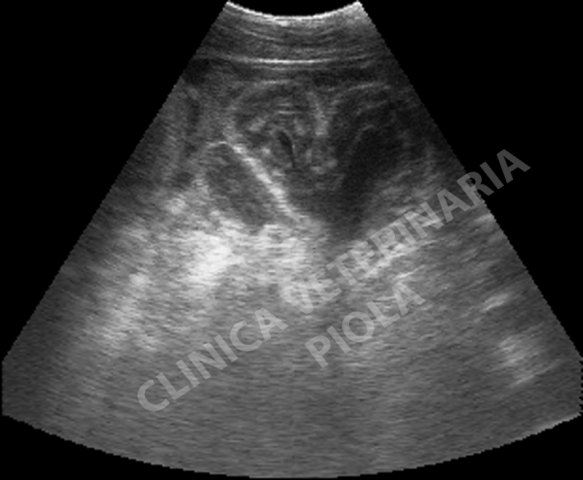

cieco edematoso per torsione